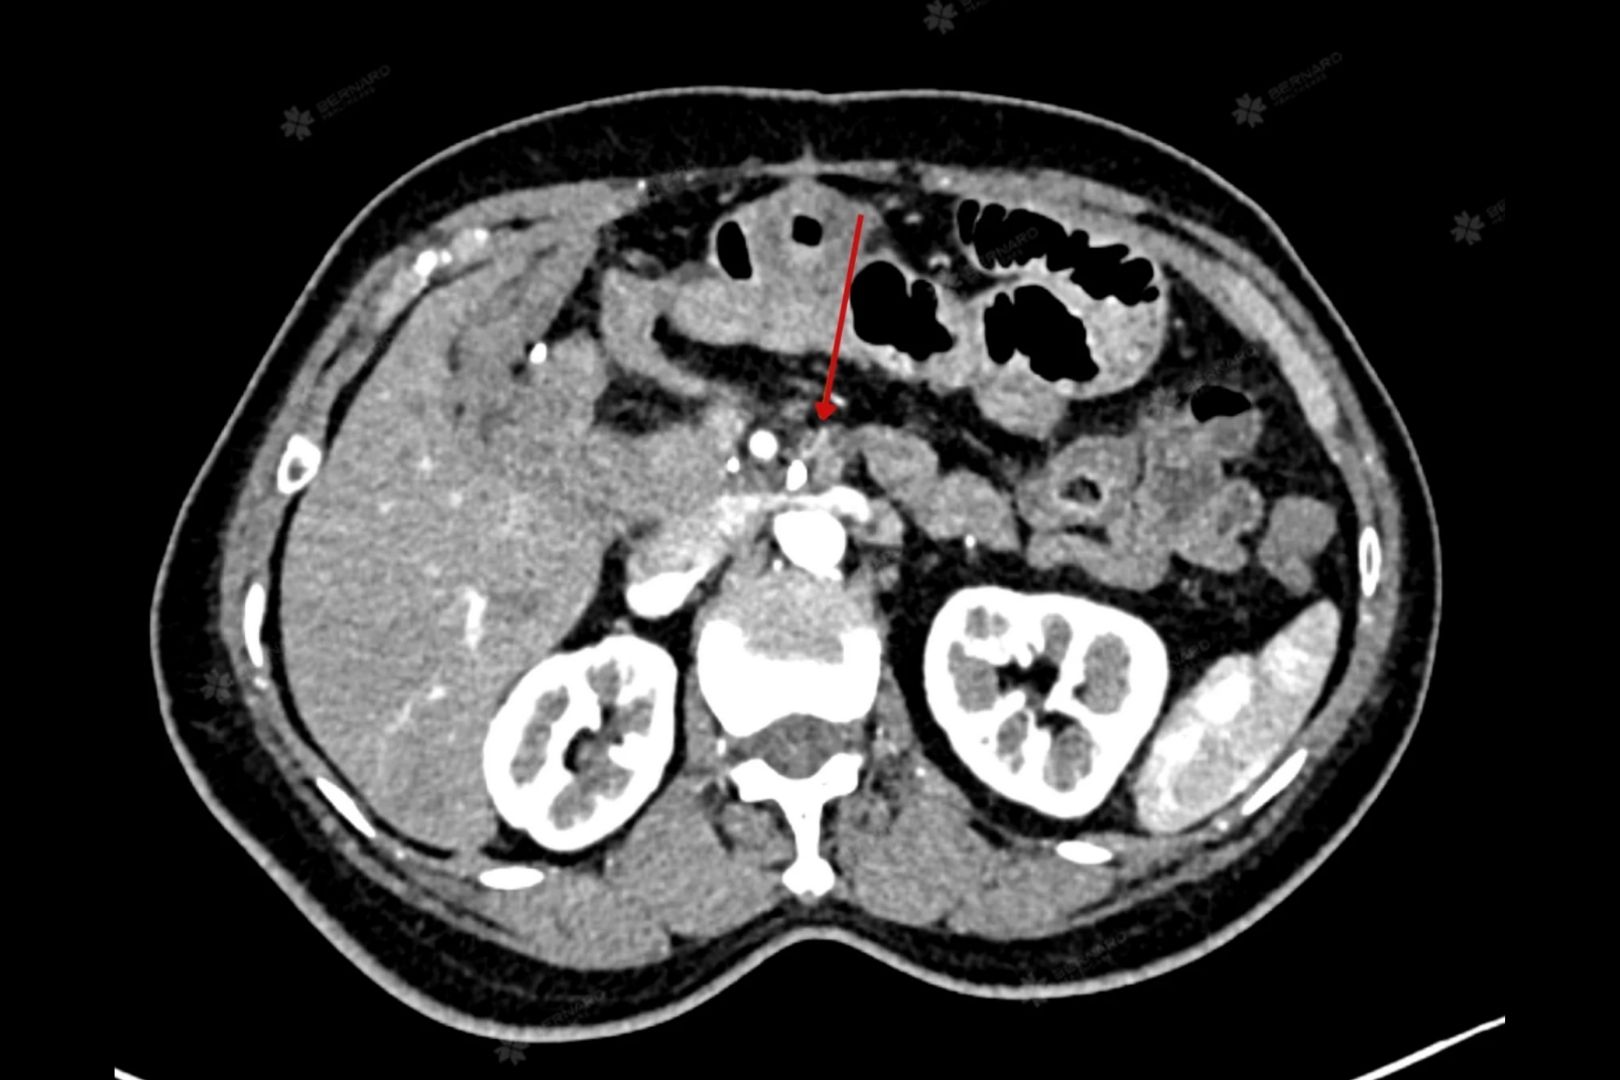

Bệnh nhân N.K.C. (59 tuổi) từng được chẩn đoán carcinoma tuyến bóng Vater kiểu mật tụy, giai đoạn IIIb, hiện đang trong giai đoạn theo dõi sau điều trị. Dù đã thực hiện chụp CT bụng tại cơ sở điều trị, bà vẫn muốn đảm bảo kết quả được kiểm chứng bởi các chuyên gia hàng đầu, nên đã tìm đến Hệ thống Y khoa chuyên sâu Quốc tế Bernard - đơn vị hợp tác đọc chéo hình ảnh với Bệnh viện Đại học Yamanashi (Nhật Bản).

Thông qua hệ thống PACS kết nối trực tiếp, hình ảnh CT Scan của bệnh nhân được gửi sang Nhật Bản. Chỉ sau thời gian ngắn, giáo sư - bác sĩ chẩn đoán hình ảnh Bệnh viện Đại học Yamanashi đã phản hồi báo cáo chi tiết.

Kết quả trả về nêu rõ, không phát hiện khối u tái phát tại phần tụy còn lại sau phẫu thuật cắt khối tá tụy. Tuy nhiên, vùng mô mềm quanh thân tạng và động mạch gan chung có biến đổi hậu phẫu, cần theo dõi sát để loại trừ khả năng tiến triển bất thường.

Ngoài ra còn ghi nhận một số hạch to rải rác vùng cạnh động mạch chủ bụng, chưa có bằng chứng xâm lấn mạch máu nhưng không thể loại trừ hoàn toàn nguy cơ di căn.